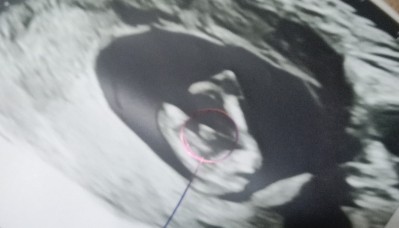

Bizim bu seki bacak arasi

Yan yuklendi resim